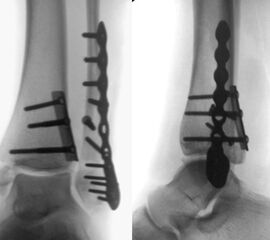

Die Versorgung von AO 44-B Frakturen erfolgt über einen längsverlaufenden lateralen Zugang. In der Regel gelingt eine suffiziente Stabilisierung mittels interfragmentärer Zugschraube (bei langem Frakturverlauf ggf. 2 Zugschrauben) und einer zusätzlichen Neutralisationsplatte (Abbildung 9 & 10).

Bei multifragmentären Frakturen (AO 44-B2.3) oder bei schlechter Knochenqualität sollte die Versorgung mittels winkelstabiler Plattenosteosynthese erwogen werden (Abbildung 11 & 12).